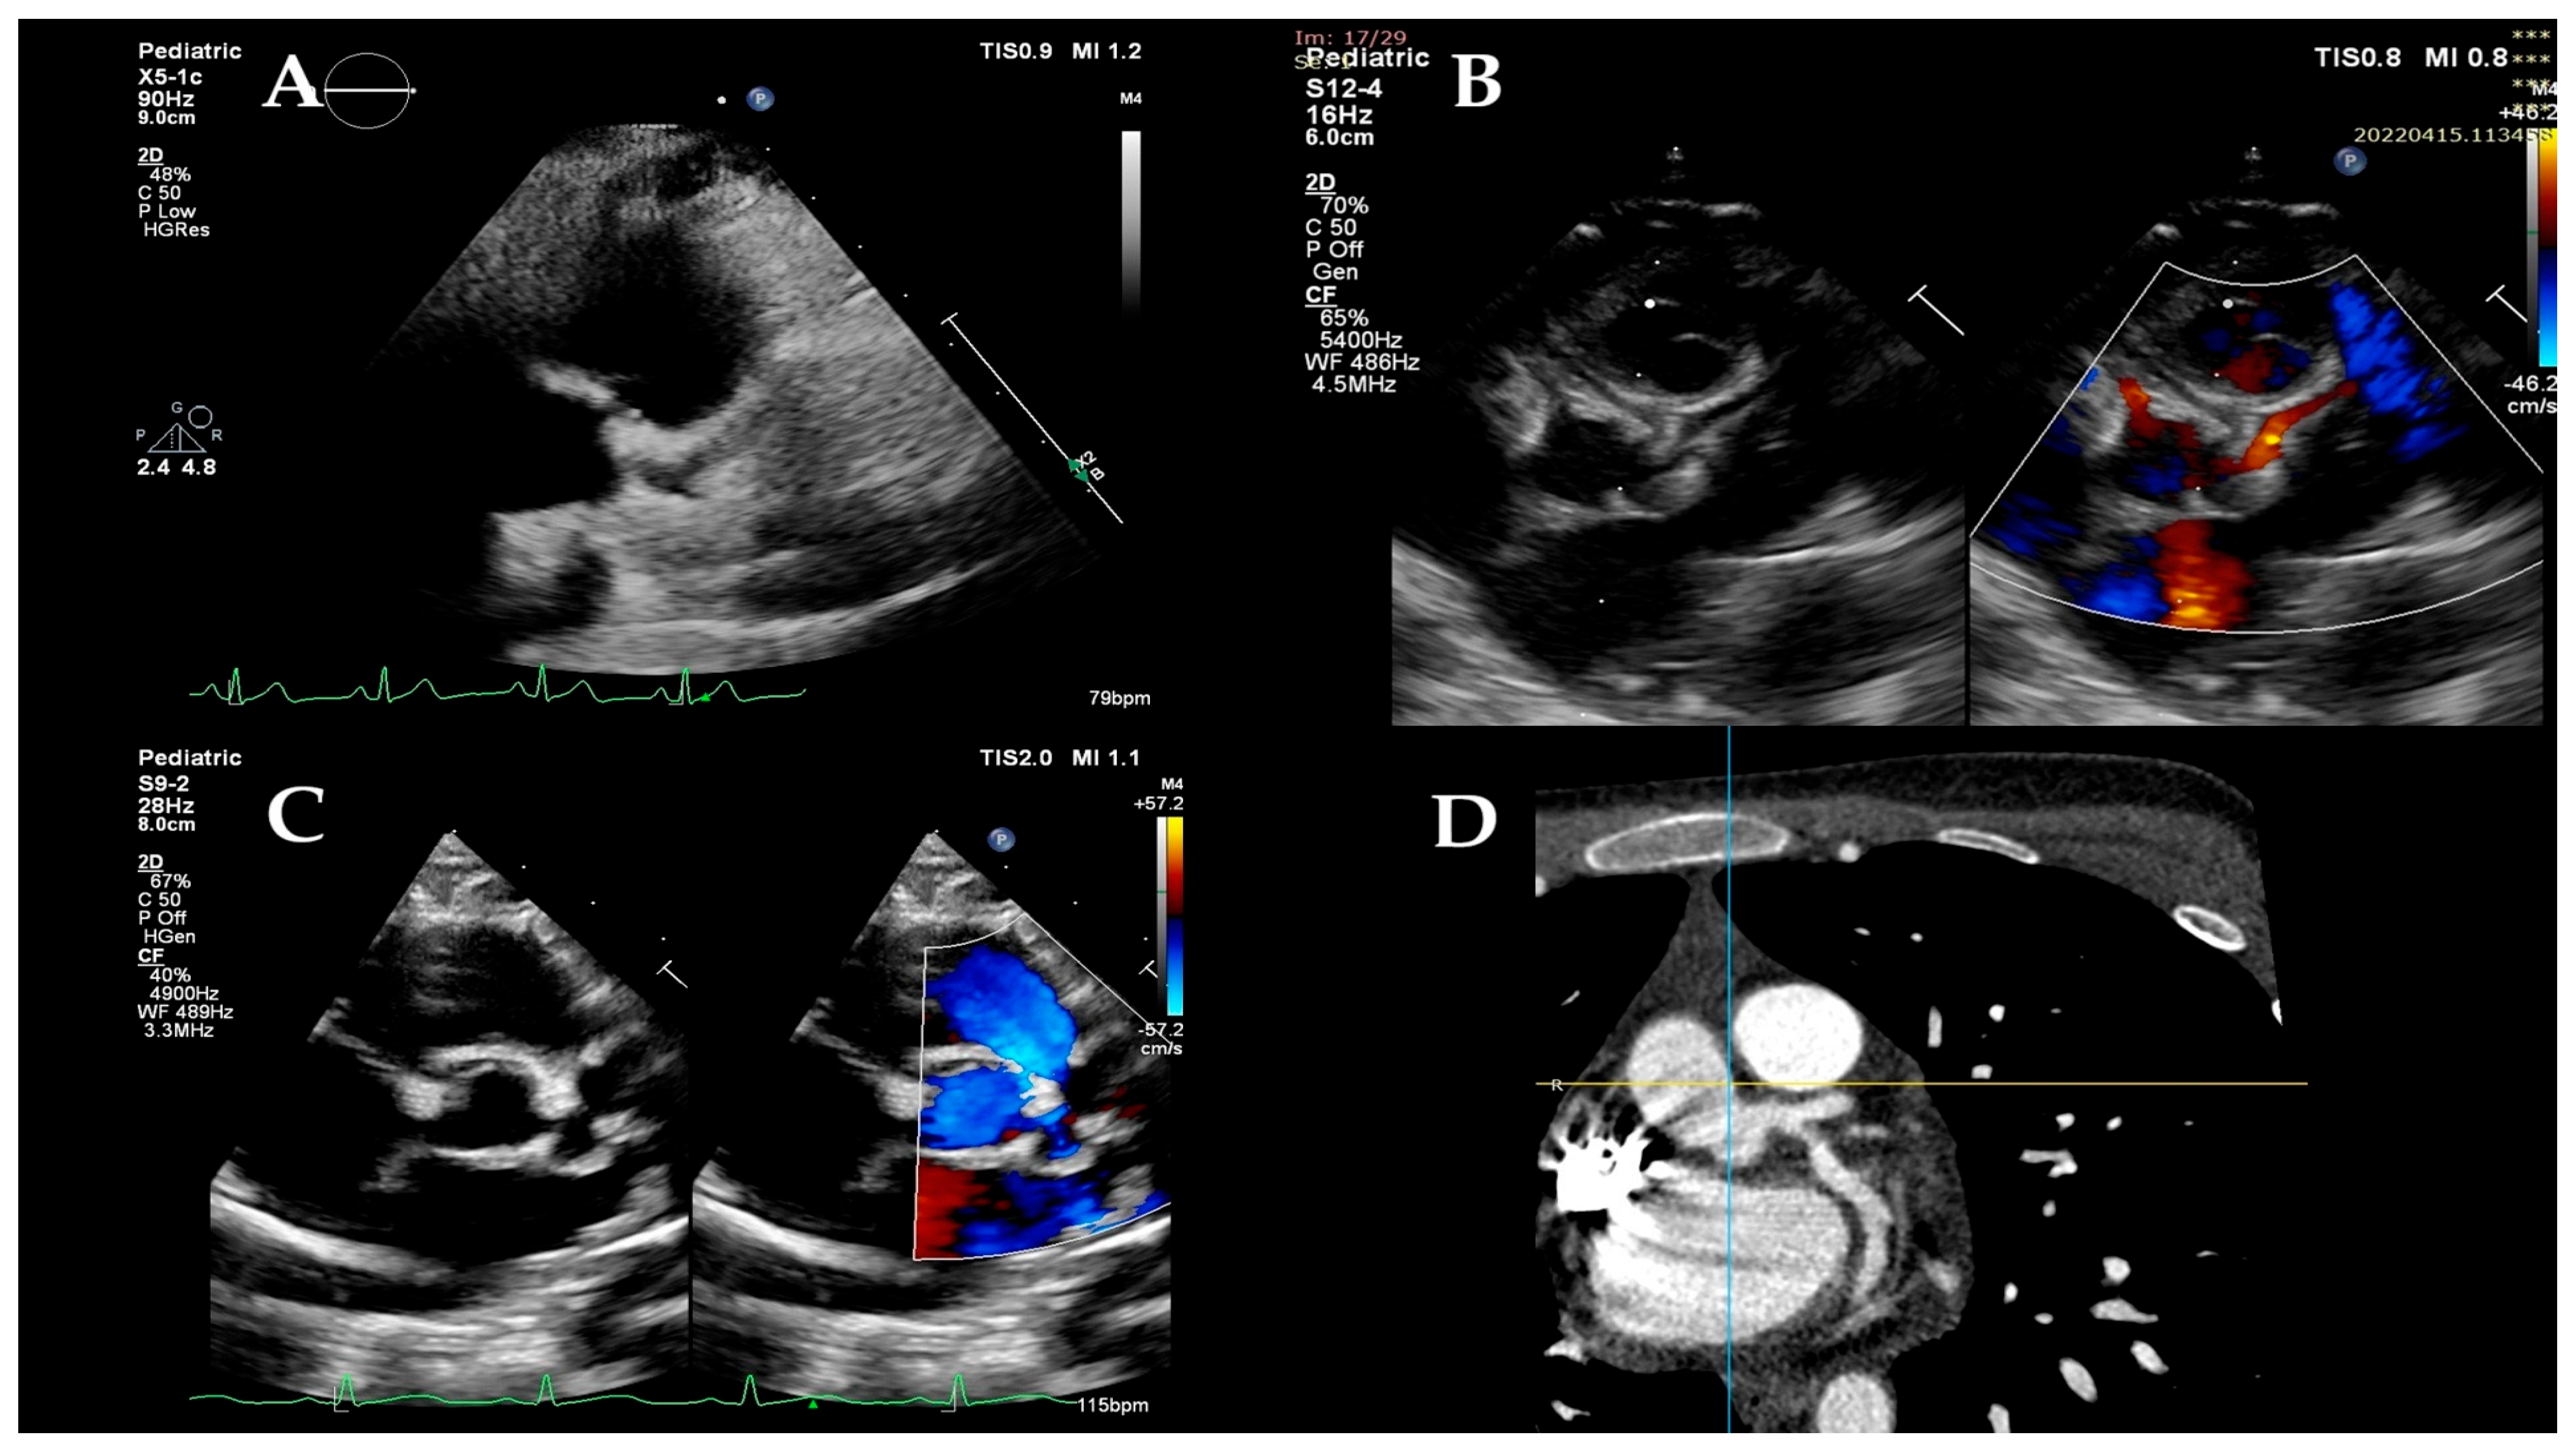

2.2. Conventional Echocardiographic Examination

| Cardiac manifestations | ||

| LV dysfunction (LV-EF: <50/49–40/<39) | 12 (n = 7/n = 2/n = 3) | 54.54 (31.81/9.09/13.63) |

| mitral regurgitation | 20 | 90.90 |

| pericardial effusion | 21 | 95.45 |

| coronary involvement | 8 | 36.36 |

| basal septal dyskinesia | 22 | 100.00 |

| mitral valve regurgitation | 20 | 90.90 |

| mitral valve regurgitation > mild | 6 | 27.27 |

| tricuspid valve regurgitation | 17 | 77.27 |

| tricuspid valve regurgitation > mild | 2 | 9.09 |

| coronary artery (CA) dilation | 8 | 36.36 |